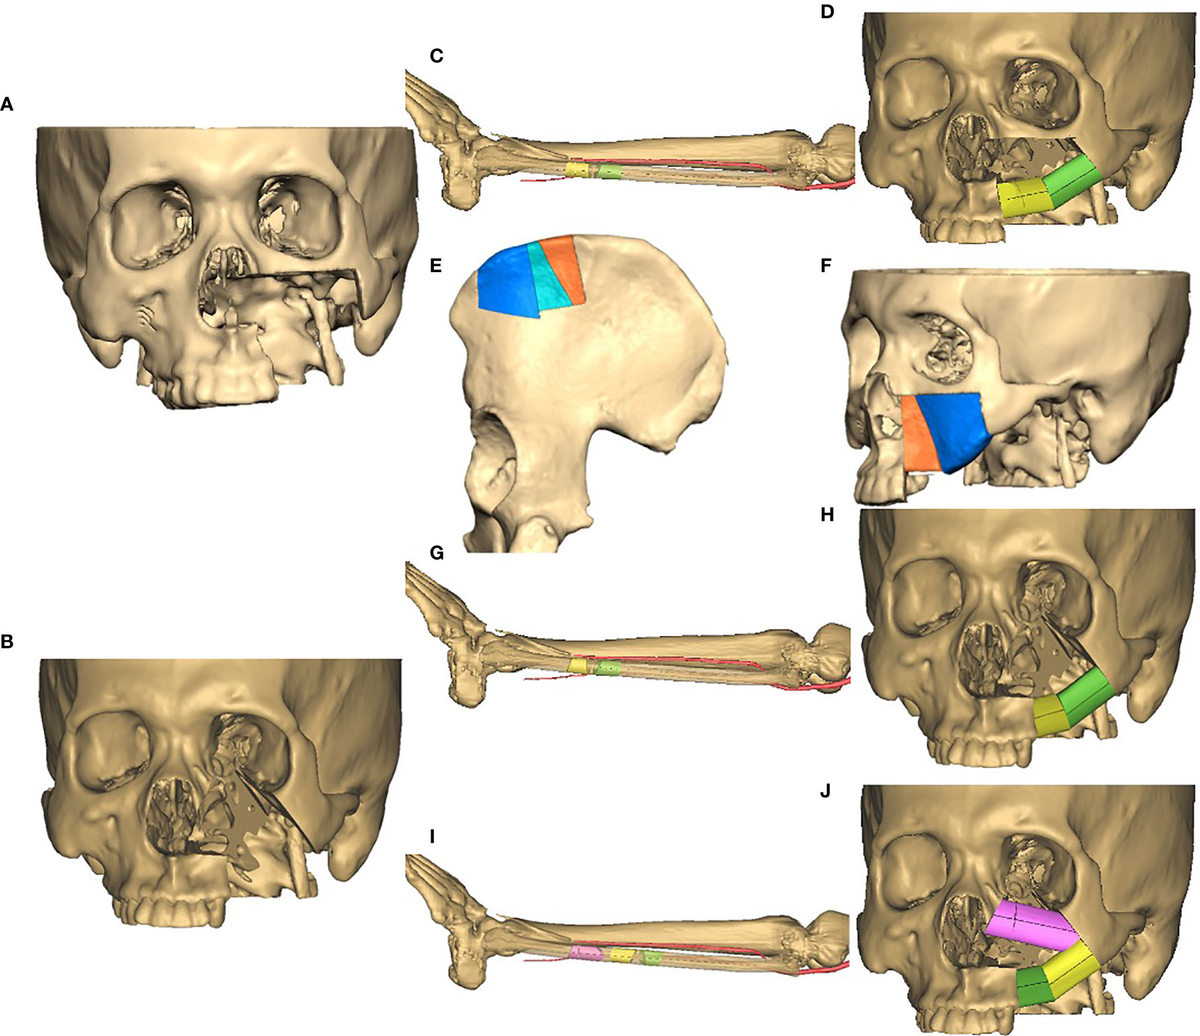

Maxilla-Oriented Implantology 多数歯欠損・無歯顎症例への。Prosthetically Driven Approach to Post-Ablative Maxilla。This patient previously underwent maxillectomy and free。多数歯欠損・無歯顎症例に特化したインプラント治療の専門書。。Rehabilitation of Maxillectomy Patients Using Zygoma。- タイトル: MAXILLA-ORIENTED IMPLANTOLOGY- 著者: 林 彦奈, 武田 孝之, 桜井 保幸, 森田 薫造- 内容: 多数歯欠損・無歯顎症例のインプラント治療- 定価: 22000円ご覧いただきありがとうございます。❤️❤️❤️❤️補綴の診断と予後❤️❤️❤️❤️役に立つ臨床ヒントと反省